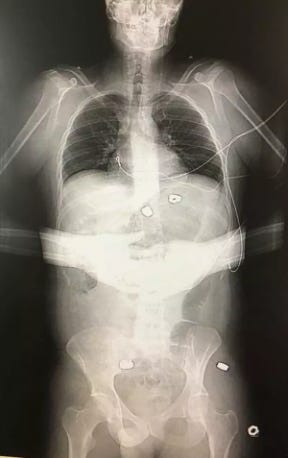

Strangely, although no such X-ray was contained in the medical evidence provided to the Court, one did appear in a LADbible report on the first anniversary of the Manchester Arena incident:

“Martin Hibbert,” reads the LADbible caption.

As Mark Conlon has pointed out, the teeth in the X-ray do not match those of Hibbert in photographs of him smiling.

Source: Mark Conlon

Yet, there is no obvious damage to the arms, throat, or jaw, or of shrapnel embedded in the face, in the above X ray. Nor is the image time-stamped, nor does it identify Martin Hibbert. Moreover, as Hall told the Court,

It cannot be deduced from the X ray, without a lateral view, whether the alleged shrapnel is inside the body, or not. The shrapnel could be on top of the body, underneath the body or possibly even using computer software.

In sum, there is no reason to trust the authenticity of the image.

Tellingly, the claimants did not enter the LADbible X-ray into evidence. They must have known that it would not withstand scrutiny. In which case, why did Martin Hibbert authorise its usage in the first place?